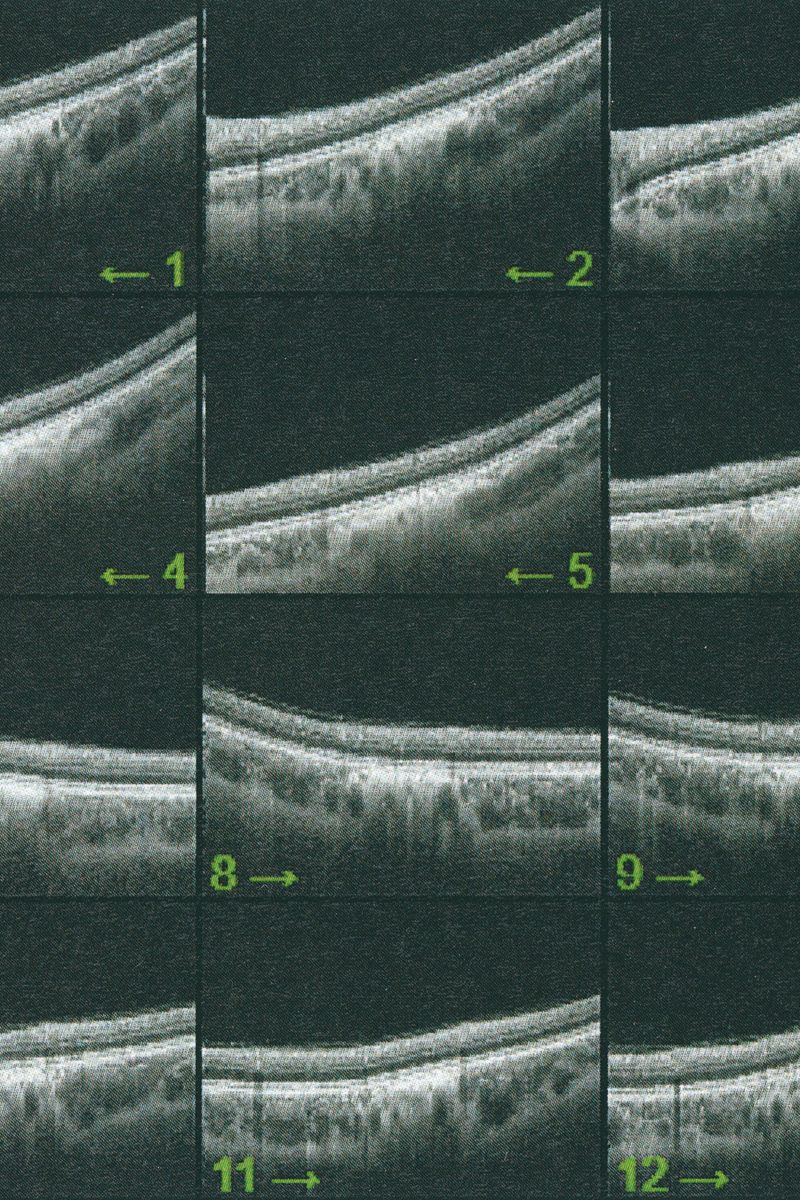

© Eugenio Pancaldi - Image from the Collirio photography project

Le Regard, George Salles. The first book in which is presented the idea of a visuality altered by culture and technology and thus historically situated.

Collirio is the photographic project I presented for my BA degree at ISIA Urbino. I designed a book (22x29.5cm, 160pages) with text pages and transparent paper inserts and a printed canvas-like dust jacket. A photographic reference scale ruler has been applied on the cover of each of the copies.